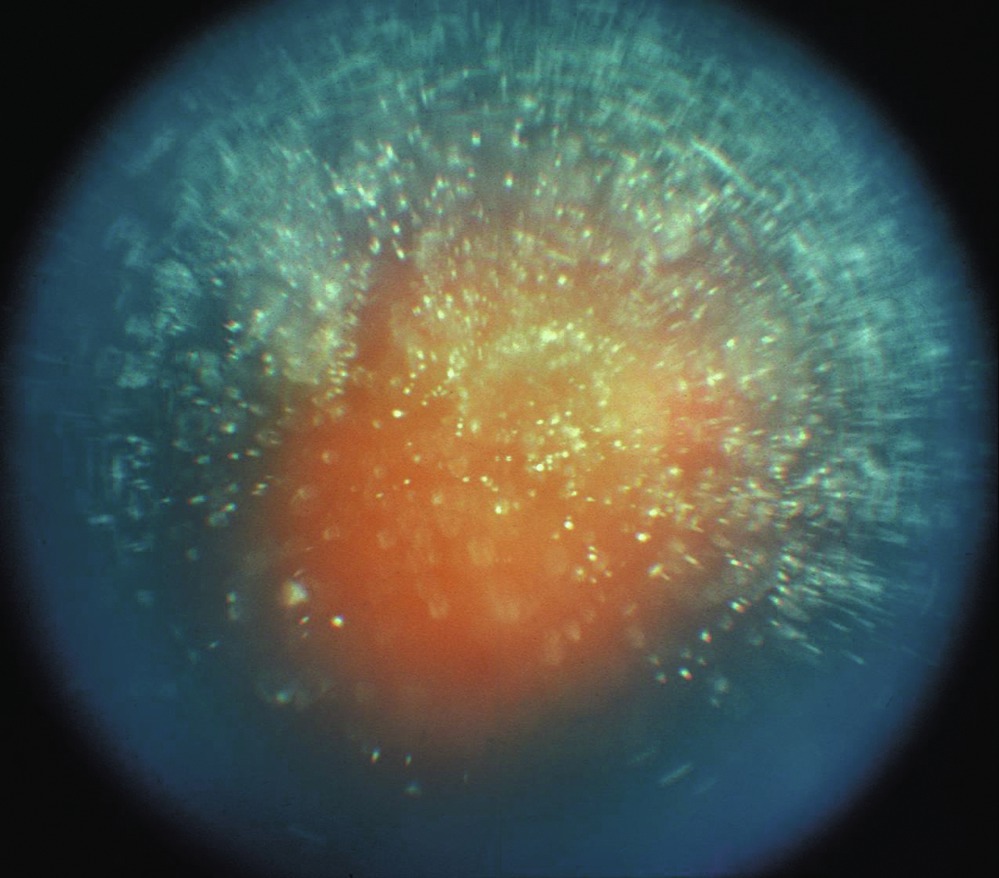

Hyalopathie astéroïde ou dégénérescence astéroïde du vitré

Dans la hyalopathie astéroïde, de petites particules blanches composées de complexes calciques riches en phospholipides sont retrouvées dans un vitré par ailleurs normal (fig. 16-9). Des études cliniques ont confirmé une relation entre la hyalopathie astéroïde et le diabète ainsi que l'hypertension artérielle. L'incidence de la maladie est de 1 sur 200 personnes. Elle survient le plus souvent chez les personnes de plus de 50 ans. La maladie est unilatérale dans 75 % des cas, et la baisse d'acuité visuelle est rare. Lorsque la dégénérescence astéroïde du vitré masque les détails du fond d'œil et qu'une pathologie est suspectée, en général, la qualité de l'angiographie à la fluorescéine n'est pas altérée et permet de détecter les anomalies rétiniennes. Parfois, une vitrectomie peut être nécessaire pour éliminer les opacités afin de faciliter le traitement des anomalies rétiniennes sous-jacentes telles que la rétinopathie proliférante. De nombreux yeux présentant une hyalopathie astéroïde ont une interface vitréorétinienne anormale avec des adhérences vitréorétiniennes. Ces adhérences augmentent le risque de formation de déchirure rétinienne iatrogène pendant la vitrectomie.

Figure 16-9

Rétinophotographie couleur d'une hyalopathie astéroïde.

(Remerciements au Dr Hermann D. Schubert.)